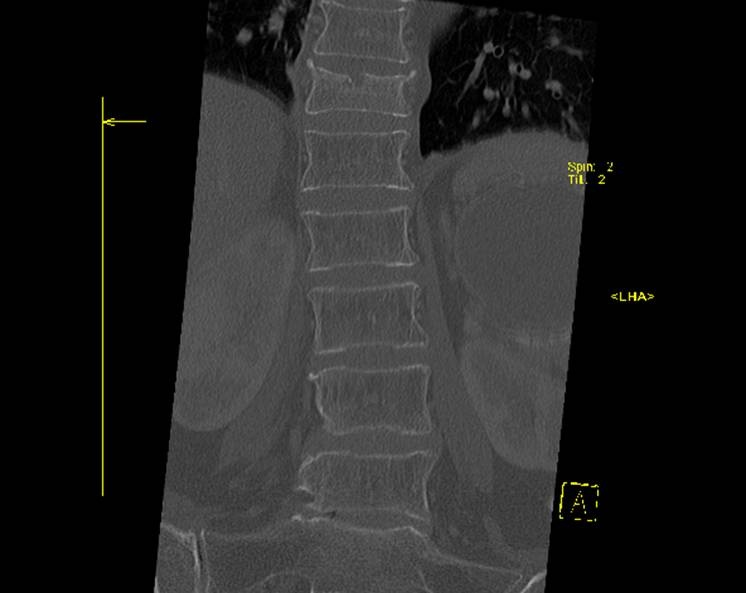

> Пациентка, 1934 г.р., постует 8 апреля к травматологам... упала дома на

> спину... сильные боли в области перехода грудного в поясничный отдел

> позвоночника... Рентген... (первые две картинки)

> Выполняют КТ-позвоночника... (Третья и четвертая картинки)